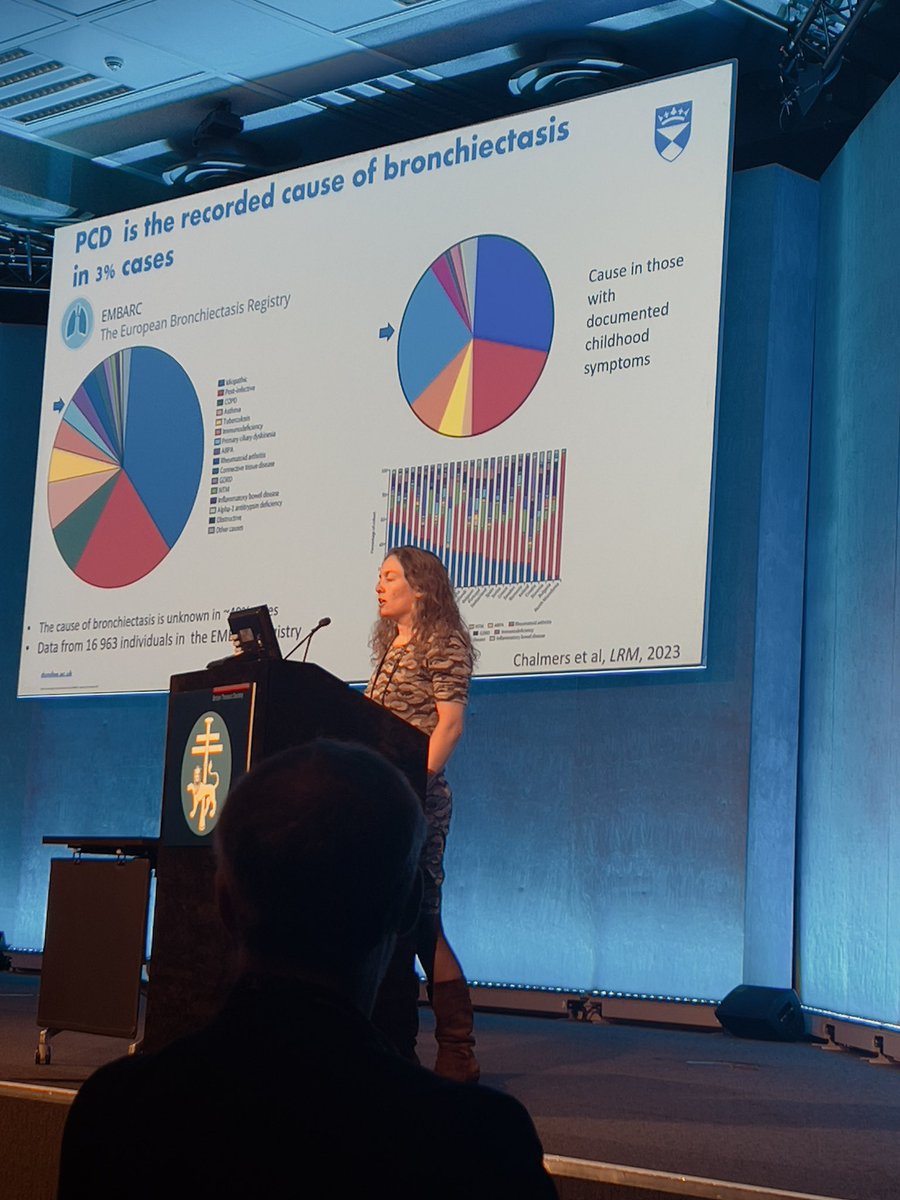

RESPIRATORY PHYSIOS ARE PLAYING CENTRAL ROLES AT THIS YEAR'S BRITISH THORACIC SOCIETY SUMMER MEETING Pearlene Antoine-Pitterson, Enya Daynes and Róisín Cahalan have key roles at the British Thoracic Society event: physioupdate.co.uk/news/respirato… @roisinc1 British Thoracic Society (BTS) Enya Daynes